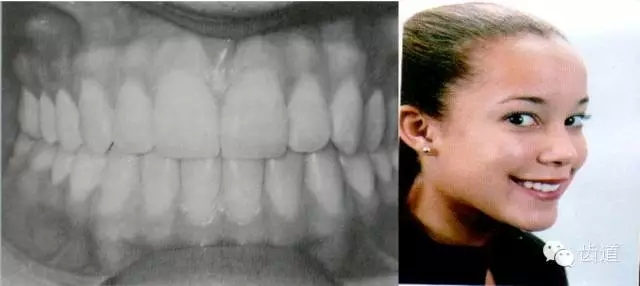

上頜6的近中頰尖正對(duì)下頜6的頰溝

上頜6的近中舌尖位于下頜6的中央窩內(nèi)

下頜6的遠(yuǎn)中頰尖位于上頜6的中央窩內(nèi)

典型面形